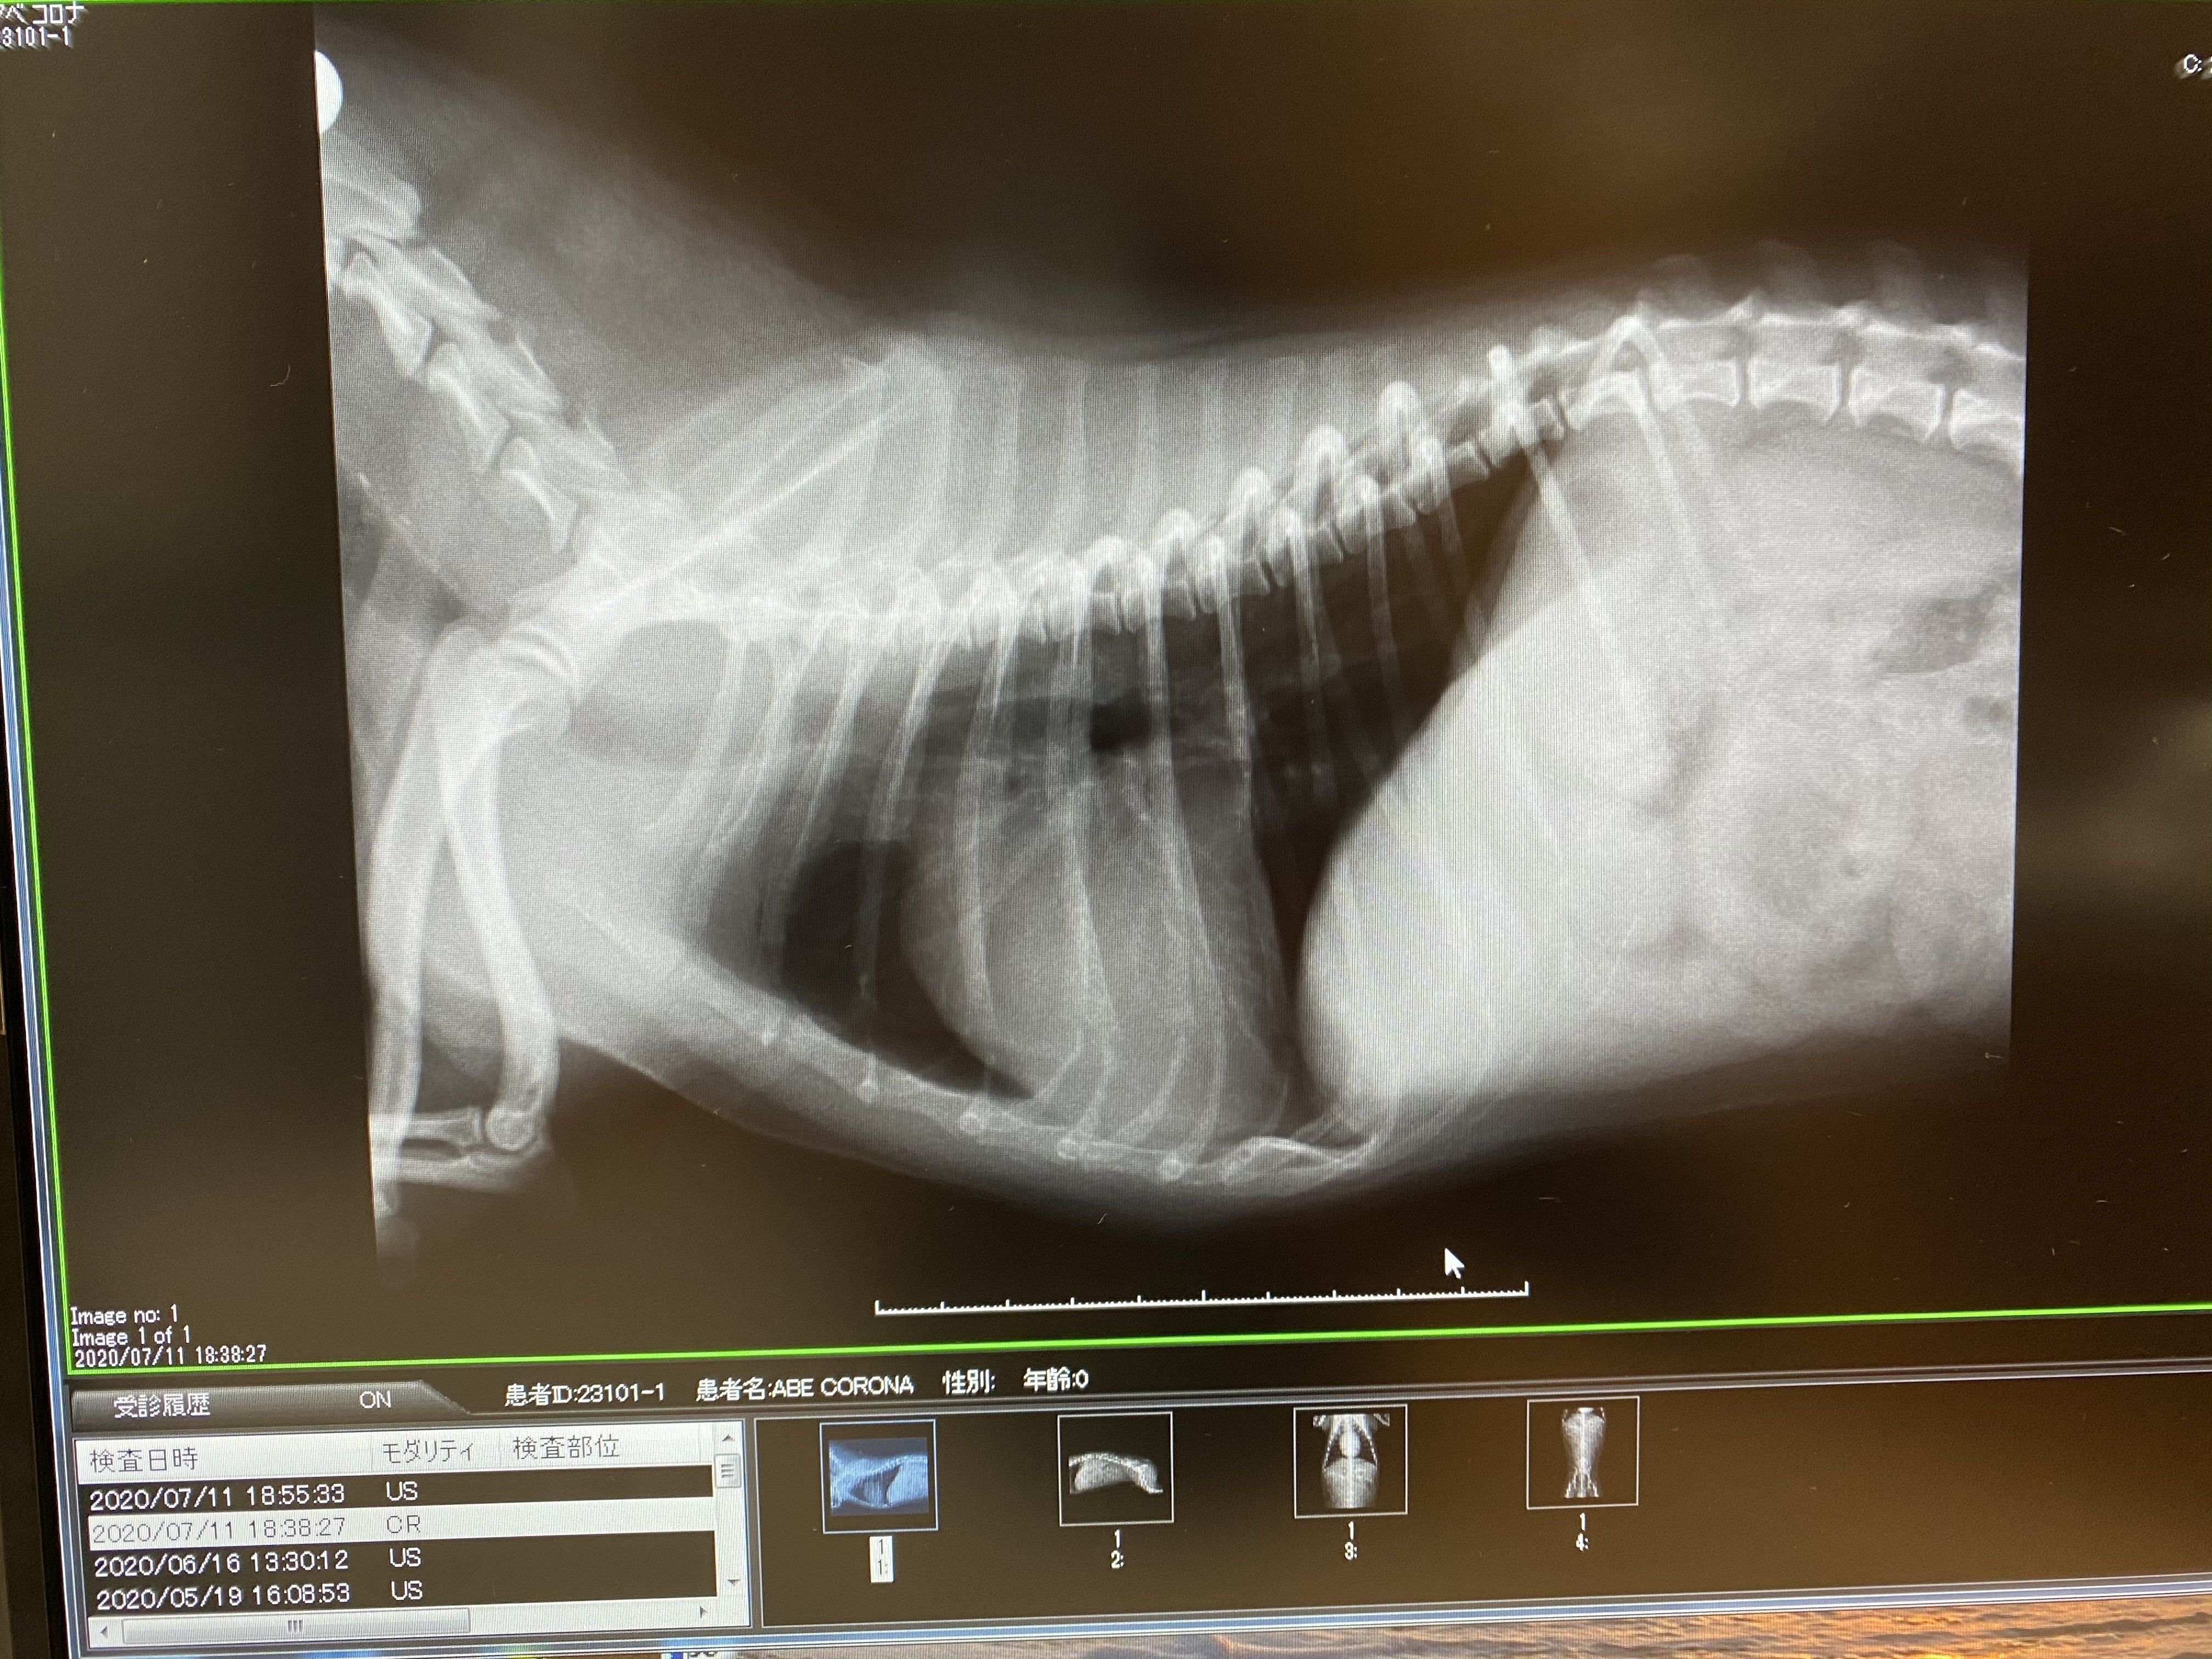

前回の心臓と気道

以前は心臓がパンパン過ぎて気管を押し上げ気道が狭くなっていたのが…

心臓で圧迫されていた気管が今は下がっているのがわかります今回のレントゲンを見てわかる通り、押し上げられていた気管が下がり、気道が確保されていました!

最近は咳き込むことや息苦しそうな仕草も数える程しかしなくなって、何もしなくてもずっと息が荒くハァハァしてたのもほとんど無くなってきていました。